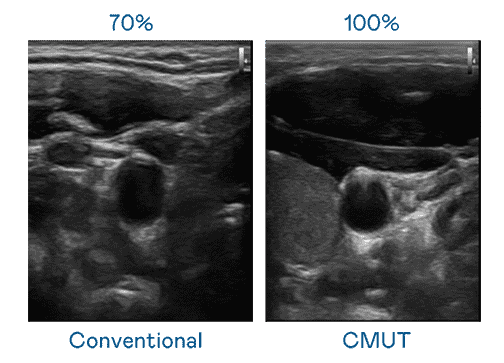

CMUT 技术是一种用电容式微机电元件来产生超音波讯号的技术。。。。与传统 PZT 压电式技术相比,,CMUT 频宽增加 30%,,更宽频的超音波讯号让影像解析度大幅提升,,,,是实现高影像品质医疗超音波扫描、、、、促进精准医疗发展的关键技术。。。

大频宽带来超清晰影像

超音波影像的解析度高低,,,首先取决于探头能发出的讯号频宽。。。。开云电子 CMUT 可提供高清晰的超音波讯号,,,提供高频宽、、、、高灵敏度、、、、影像纹理细节更高的超音波影像,,,,协助医护人员缩短影像判读时间及利用精准的医疗影像进行诊断。。。